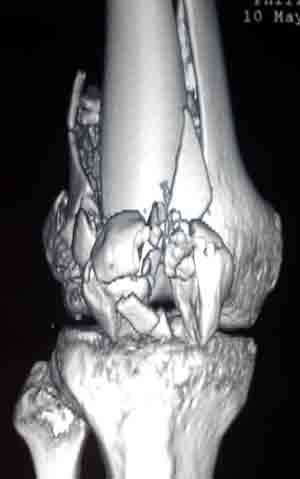

La artroscopia de rodilla es un procedimiento de mínima invasión en el que se hacen dos pequeñas incisiones de 4 mm a cada lado de la rodilla. Este método nos permite reparar lesiones de meniscos, que es la patología más común en larodilla; lesiones ligamentarias, lesiones del cartílago articular. Es útil también como método auxiliar en algunos procedimientos combinados en donde se utiliza cirugía convencional para fracturas y con control artroscópico se cuida que la articulación quede en óptimas condiciones.

Actualmente la lesión de Ligamento Cruzado Anterior (LCA) ya no implica un problema su reparación y aún en deportistas de alto rendimiento pueden retornar a su alto nivel deportivo. La cirugía sin embargo, requiere de alta precisión para su éxito, por lo que requiere de una alta experiencia por parte del cirujano ortopedista. El procedimiento se realiza por tres incisiones, dos de 4 mm y una de 1 a 2.5 cm, por una de las incisiones menores se introduce la cámara con la que se revisa toda la articulación, por otra de las pequeñas incisiones se introducen los instrumentos necesarios y por la tercera se obtiene y se tuneliza el nuevo ligamento.